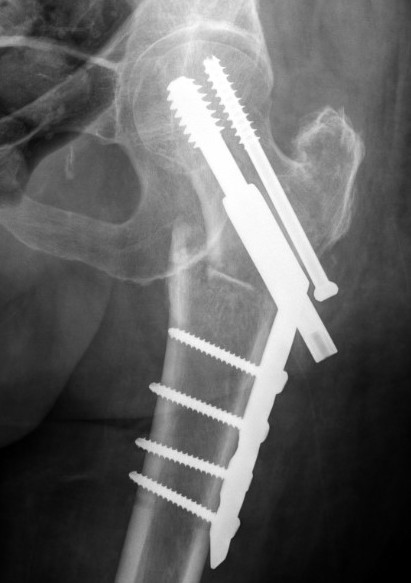

Sliding hip screw/dynamic hip screw

Dynamic hip screw

Mechanism

Plate is a lateral tension band whilst the sliding screw allows controlled fracture impaction

Options for improving stability

b. Trochanteric stabilization plate

Theory

- buttresses the GT and prevents lateral displacement